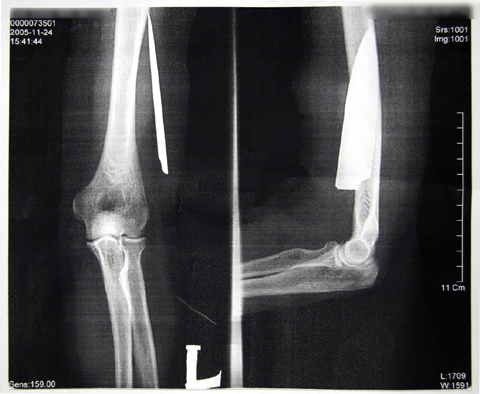

병원측은 환자의 팔꿈치 속에 약 11cm의 칼날이 박혀있음에도 불구, 22일여의 치료과정 동안 외상만을 치료해 온 것으로 드러났다.

이어 “11월 24일 치료를 위해 찾은 병원에서 상태를 이상히 여긴 담당의사가 메스로 상처부위를 터트려 부풀어 있는 핏물을 뽑아냈다”며 “상처부위를 마취 후 집게를 넣어 휘저어 보니 이물질이 있어 X-Ray를 찍어본 결과 11cm의 칼날이 들어있어 경악했다”고 당시의 상황을 설명했다.